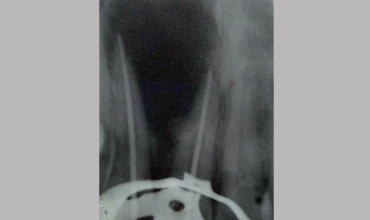

Surgical Management Of Large Periapical Cyst